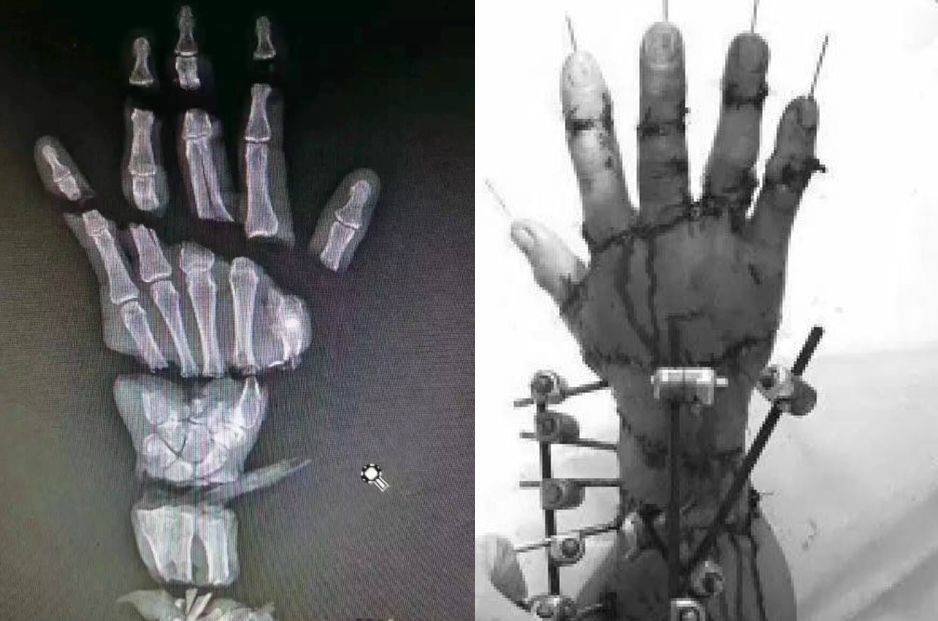

八、今天,我们的精湛的外科手术甚至可以给一个被截成整整5段的手指完全还原接上,让人叹为观止。

85.jpg